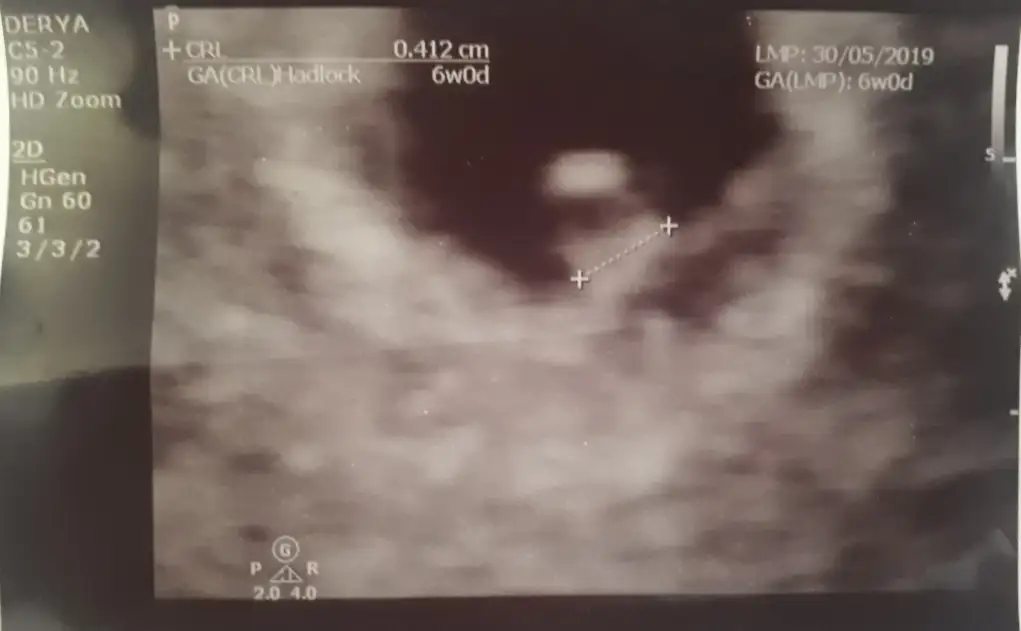

Kanama alanım. İşaretlenmiş bebeğin tam altındaki koyu alan. Bu şekilde olup sağlıkla ilerleyyen veya kaybeden var mı. Tüp bebekle olmuştu çok acı çok üzüntü çektim inşallah sağlıklıdır. Allahım hepimize yardım etsin. 6 haftalık daha